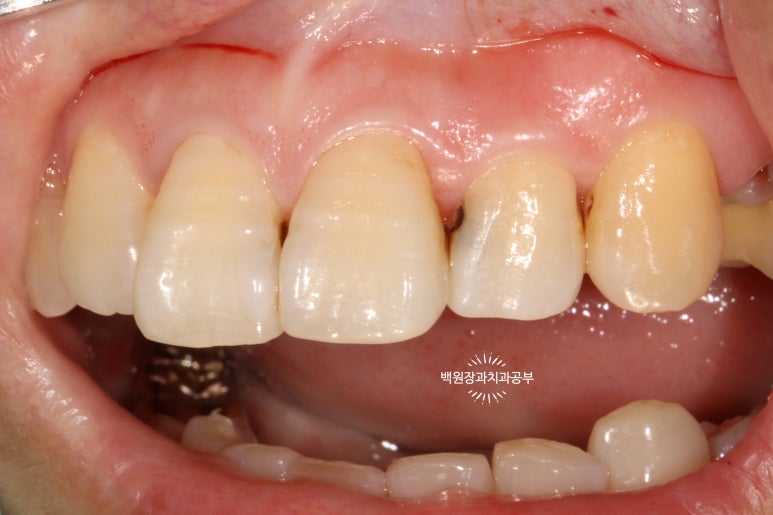

서론이 길었네요. 60대 여자 환자분이시고 위 앞니 사이사이에 있는 인접면 충치 치료차 내원하셨습니다.

정면을 보면, 치아 사이사이에 있는 충치가 얼핏 보이실거에요!

하얀것은 치아고 까만것은 충치라는걸 유치원생도 다 구분할 수 있을거에요. ㅎㅎㅎ

위턱 앞니의 사이사이마다 인접면 충치가 보이네요...

더 확실하게 보여드리기 위해 고개를 살짝 돌려서 보면..

고개를 돌려서 보면 인접면 충치를 더 잘 확인하실 수 있습니다!

집에서 확인해 보실 때도 고개를 돌려서 보셨었겠죠?

치료 전과 치료 후를 쉽게 비교하실 수 있도록, 치료 직전 찍어놓은 사진이에요.

상악 중절치와 측절치 그리고 견치에 옆면 모두에 충치가 있습니다.